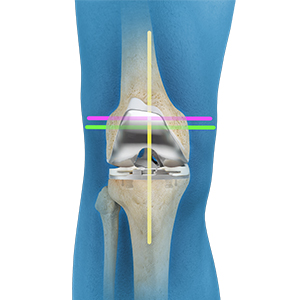

• Kinematic Alignment Total Knee Replacement

Kinematic Alignment Total Knee Replacement

Kinematic alignment (KA) is a customized technique for total knee arthroplasty (TKA)...